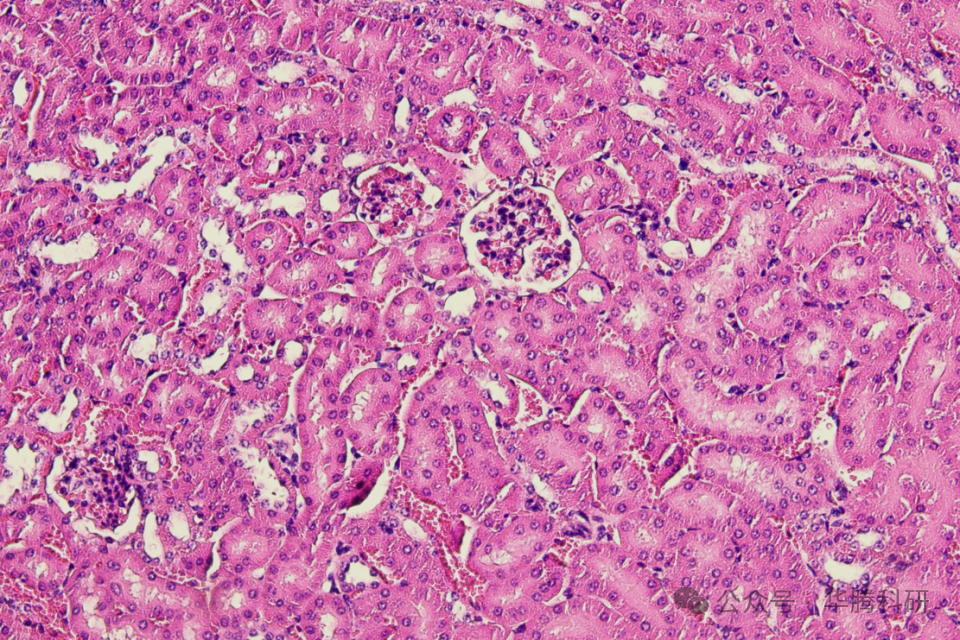

HE染色结果显示,假手术组小鼠肾小球结构清 晰、肾小管紧密排列,未见明显炎性细胞浸润。模 型组小鼠肾脏组织出现损伤,肾小球形态结构异 常,肾小管刷状缘缺失及小管扩张,临近小管细胞 与上皮细胞边界不明显,间质出现炎症浸润。

假手术组,40x